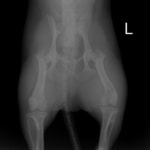

症例3:キルシュナーワイヤーのピンニングによる整復

ペルシャ猫 11ヶ月齢 雄

他院にて左大腿骨遠位の成長板骨折(salter-harrisⅠ型)が認められており、治療相談を目的として来院。当院にて、キルシュナーワイヤーを用いたピンニングにより骨折部位の整復を行いました。術後の経過は良好で、現在も経過観察中です。

術前レントゲン

術後レントゲン